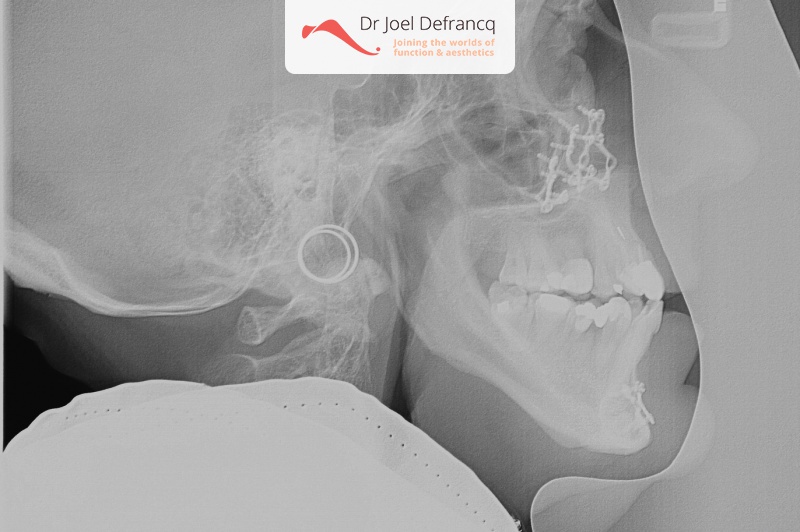

James: jaw surgery and implants - one surgery.

Diagnose van het gezicht

- Te kleine onderkaak (Overbeet)

- Asymmetrisch gezicht

Kaakchirurgie

- Verlenging onderkaak (BSSO)

- Verlenging bovenkaak (Le Fort I)

- Rotatie bovenkaak

- Onderkaak rotatie

- Kinchirurgie

Behandeling tandheelkundige implantaten

- Vaste tanden op implantaten (bovenkaak)